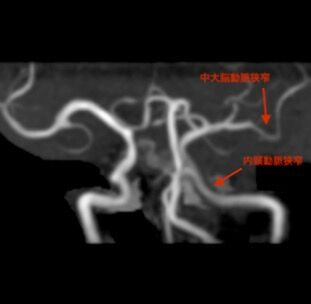

実際には、MRIと同時に撮影されたMRAでは、左中大脳動脈のM1〜2及び左内頸動脈に狭窄が認められていました。ABCD3-Ⅰスコアにおいては、同側内頸動脈(Aさんの症状は右上下肢麻痺でしたのでこれに該当します)の50%以上狭窄が+2と評価されることになっており、本当は注目すべきサインなのですが、B病院の主治医はこれを全く認識していませんでした。

実際には、MRIと同時に撮影されたMRAでは、左中大脳動脈のM1〜2及び左内頸動脈に狭窄が認められていました。ABCD3-Ⅰスコアにおいては、同側内頸動脈(Aさんの症状は右上下肢麻痺でしたのでこれに該当します)の50%以上狭窄が+2と評価されることになっており、本当は注目すべきサインなのですが、B病院の主治医はこれを全く認識していませんでした。一方、てんかんの診断には、てんかんの既往、発作時の痙攣、脳波検査等が重要です。Aさんにはてんかん発作の既往はありませんでしたし、それについて、主治医は問診もしていません。また、発見時は既にベッド横に倒れている状態であり、発作時の痙攣も現認されていません。さらに脳波検査も行われていません。